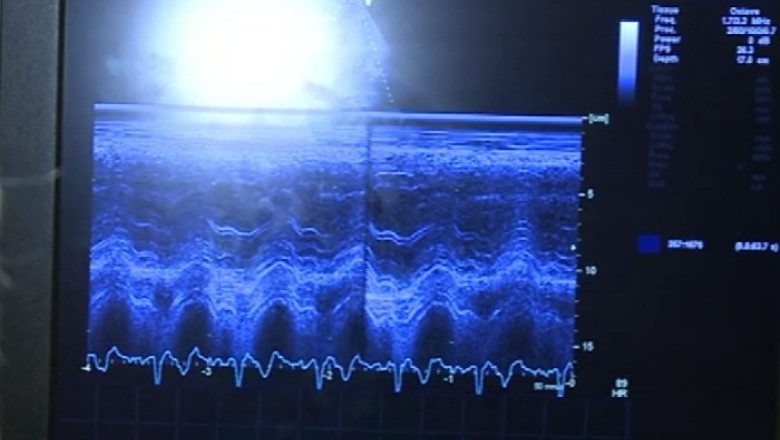

45 de ani şi o inimă deja bolnavă, ce a trecut printr-un infarct. La ecograf, medicul cardiolog vede dacă sechelele produse de atacul de inimă, survenit pe neaşteptate, sunt mari.